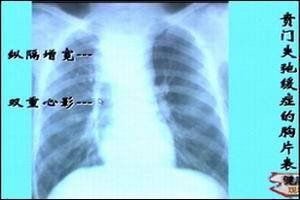

1.食管鋇餐X線造影

吞鋇檢查見食管擴張,食管蠕動減弱,食管末端狹窄呈鳥嘴狀,狹窄部黏膜光滑,是賁門失遲緩症患者的典型表現。Henderson等將食管擴張分為三級:I級(輕度),食管直徑小於4cm;II級(中度),直徑4~6cm;III級(重度),直徑大於6cm,甚至彎曲呈S形。